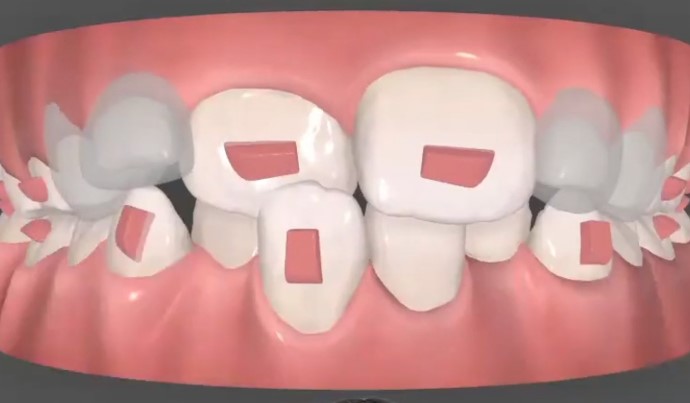

Se diseñó un tratamiento con alineadores de ortodoncia invisible, planificado de forma completamente personalizada.

La secuencia de tratamiento fue especialmente precisa y exigente:

— Descruzar la mordida de los incisivos anteriores

— Expandir las arcadas para favorecer el desarrollo óseo

— Generar el espacio necesario para la correcta alineación dental

Cada fase fue cuidadosamente planificada mediante movimientos dentarios secuenciados.

Fase 1 – Bloqueo

Fase 2 – Descruce

Fase 3 – Expansión

Fase 4 – Alineación